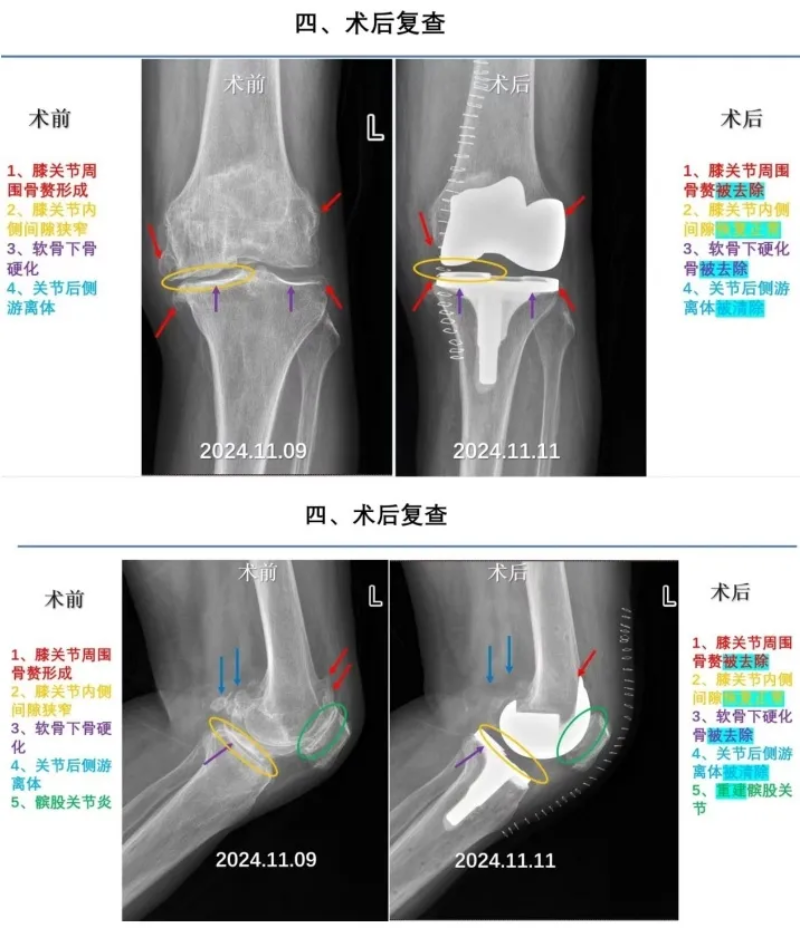

“根据你的情况,我们决定由手术机器人辅助完成这台手术。”近期,坪山区中心医院骨科学科带头人张庆主任在手术机器人的辅助下,为患有“双膝关节重度退行性骨关节病”的肖阿姨完成了膝关节置换手术。

术前,机器人精准测量出截骨量、假体型号及安放位置。术中,骨科团队在机械臂辅助下实现毫米级精确截骨。

在术者和机器人的完美配合下,手术顺利完成,整个手术过程不到一个半小时,假体位置安放良好,还成功纠正了肖阿姨的“O型腿”。

术后,肖阿姨恢复得非常好,原本无法正常行走的她,很快就在助行器的帮助下逐渐行走。

张庆表示,肖阿姨的快速康复,一方面是因为机器人辅助手术切口小、疼痛轻,另一方面是得益于以多学科综合治疗组(MDT)为主导的精细化围手术期管理模式——从术前准备、全面评估,到制定个性化手术方案、实施微创手术,再到术后康复管理等,全方位保障了患者健康,提供了高效优质的治疗体验。

机器人辅助全膝关节置换术的成功开展,推动了骨科手术向精准化、个性化、微创化、智能化发展,实现了“量体裁衣”式的个性化诊疗,为更多患者带来福祉。